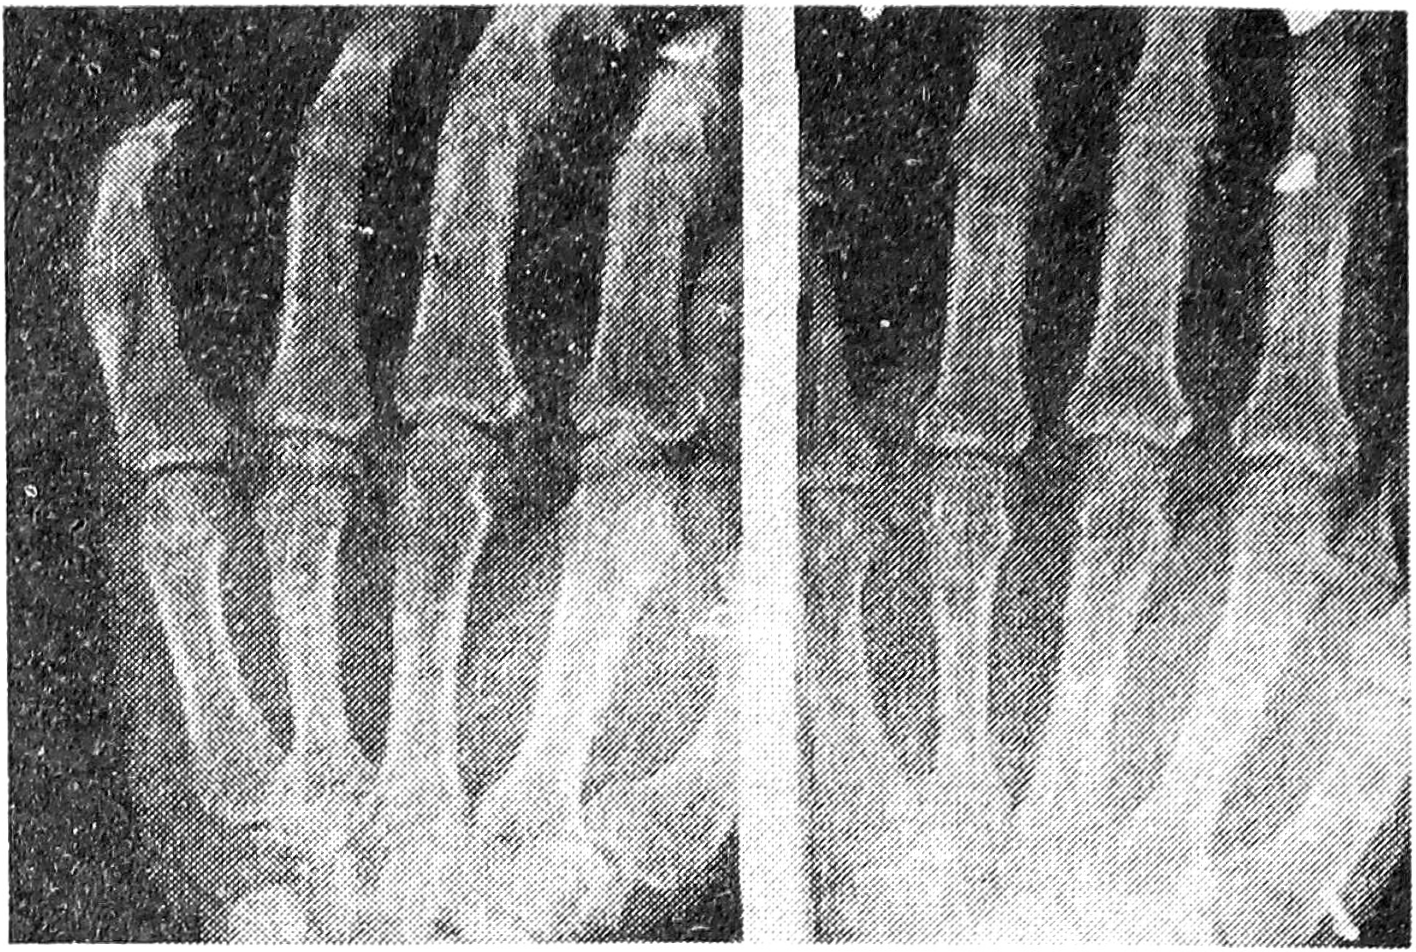

М., 45 лет (история болезни № 946), поступил в отделение хирургии кисти 05.04. 1994 г. с диагнозом: фиброзная сгибательно-разгибательная контрактура проксимального межфалангового сустава V пальца левой кисти как следствие внутрисуставного косого перелома основной фаланги (рис. 1). При падении 2,5 месяца назад на левую кисть получил закрытый косой внутрисуставной перелом основной фаланги V пальца со смещением. Репозиция отломков не производилась, 3 недели носил гипсовую повязку. По поводу фиброзной сгибательно-разгибательной контрактуры межфалангового сустава V пальца был направлен в НИЦТ “ВТО”.

Рис. 1. Рентгенограмма больного М., 45 лет, в прямой и боковой проекциях. Определяется фиброзная сгибательно-разгибательная контрактура проксимального межфалангового сустава V пальца левой кисти вследствие внутрисуставного косого перелома основной фаланги.